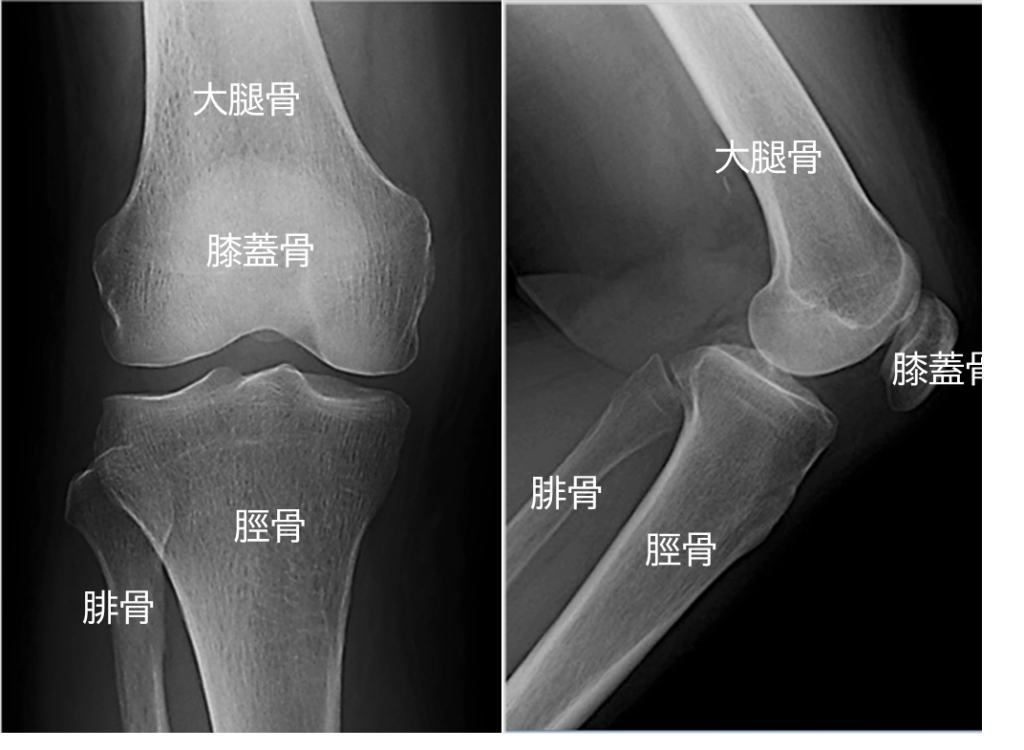

膝関節の単純X線画像です。

それぞれの骨は白字で記載しています。右の膝蓋骨は文字が少し切れておりまして、申し訳ありません。

単純X線画像では骨の濃淡がある程度わかるのみです。解剖のところでお話ししました靭帯や半月板などはすべてX線を透過しますので確認する事ができません。ですので、骨以外の靭帯や半月板といった軟部組織を見たい場合はMRI検査を行う必要が出てきます。